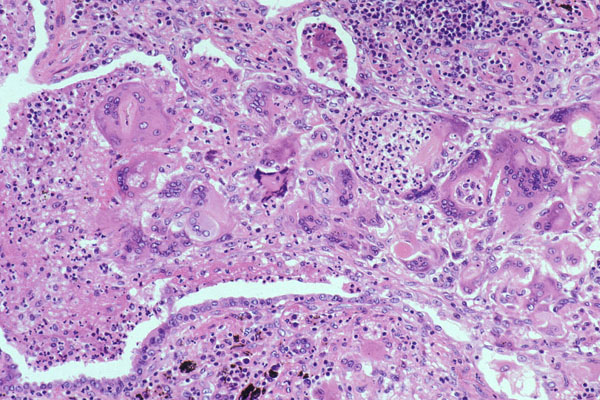

NSIP

Pathology in nonspecific interstitial pneumonia (NSIP)

(A) Cellular pattern, alveolar walls thick c uniform, cellular, inflam interstitial infiltrate; lung architecture preserved. Has small foci of organizing pneumonia

(B) Cellular pattern; cellular infiltrate mostly lymphs and a few plasma cells.

(C) Fibrosing pattern. uniform alveolar walls thickening by interstitial fibrosis; connective tissue appears same age. No honeycombing or fibroblastic foci.

(D) Fibrosing pattern; alveolar wall thickened by dense interstitial fibrosis and few chronic inflam cells; overlying pneumocytes c cuboidal hyperplasia. A few alveolar macrophages are present.